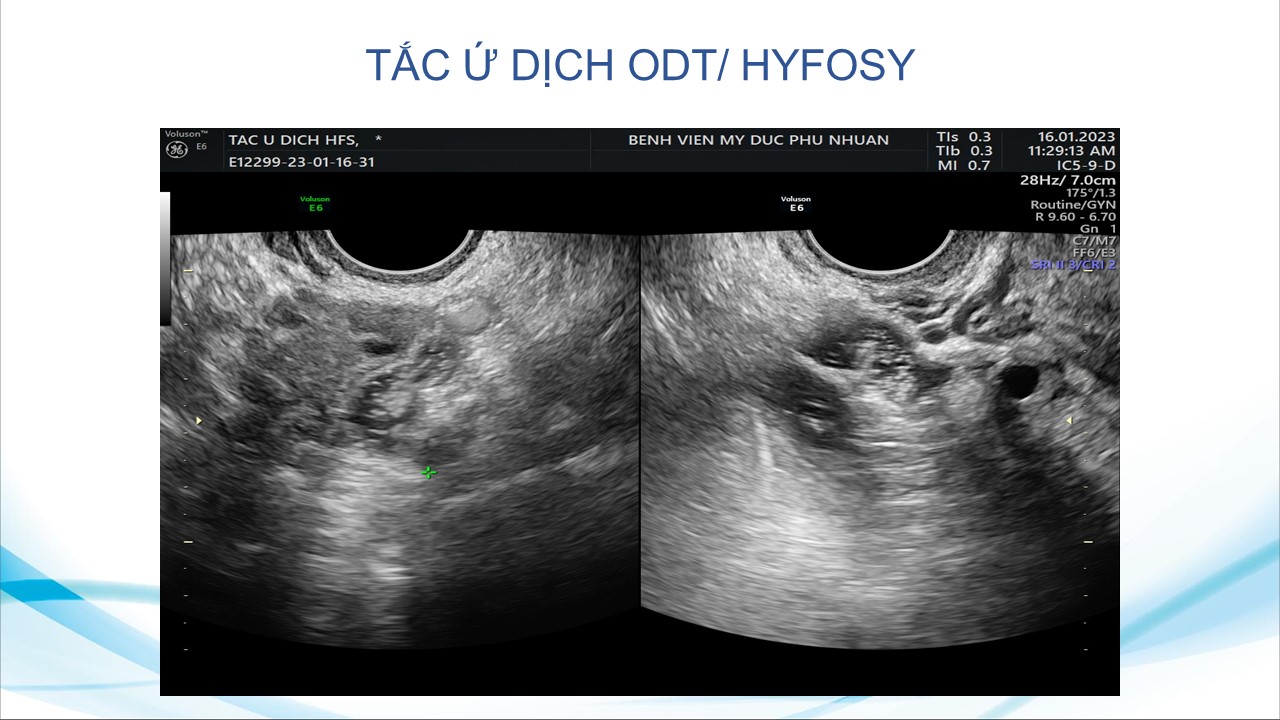

Siêu âm sử dụng chật tương phản trong phụ khoa